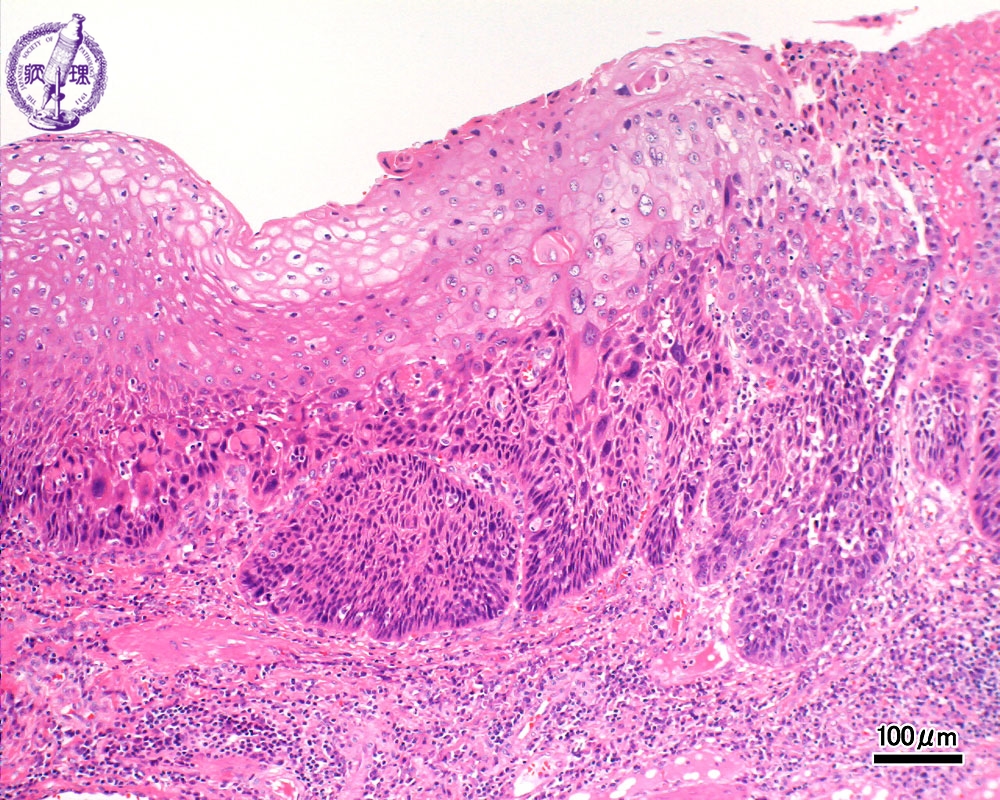

- ★(3)Esophageal carcinoma (squamous cell carcinoma)

Microscopic view (H&E stain, intermediate power): The basilar epithelium is occupied by atypical cells which show expansive invasion into the lamina propria (squamous cell carcinoma, arrow).